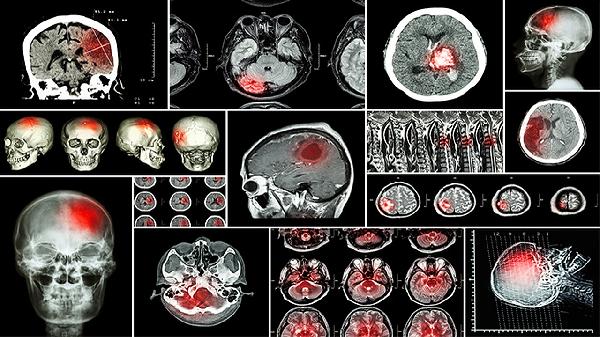

新生兒顱內(nèi)感染的恢復(fù)時間一般為2-4周,具體恢復(fù)時間受到感染類型、病情嚴(yán)重程度、治療及時性、患兒免疫狀態(tài)、并發(fā)癥等多種因素的影響。

新生兒顱內(nèi)感染的病原體主要包括細(xì)菌、病毒和真菌。細(xì)菌性感染如化膿性腦膜炎,通常需要2-3周的治療;病毒性感染如單純皰疹病毒性腦炎,恢復(fù)時間可能延長至3-4周;真菌性感染較為罕見,但治療周期更長,可能需要4周以上。感染類型直接影響抗生素或抗病毒藥物的選擇及療程。

輕度顱內(nèi)感染可能僅表現(xiàn)為發(fā)熱、嘔吐等癥狀,及時治療后恢復(fù)較快;中度感染可能伴隨腦膜刺激征或意識障礙,恢復(fù)時間延長;重度感染如出現(xiàn)腦膿腫或腦積水,可能需要手術(shù)治療,恢復(fù)時間顯著延長。病情嚴(yán)重程度與腦組織損傷范圍密切相關(guān),影響預(yù)后。

顱內(nèi)感染可能引發(fā)多種并發(fā)癥,如腦積水、腦膿腫、癲癇等。無并發(fā)癥的患兒恢復(fù)較快;若出現(xiàn)并發(fā)癥,需要額外治療,恢復(fù)時間顯著延長。并發(fā)癥的存在增加了治療的復(fù)雜性和恢復(fù)的難度。